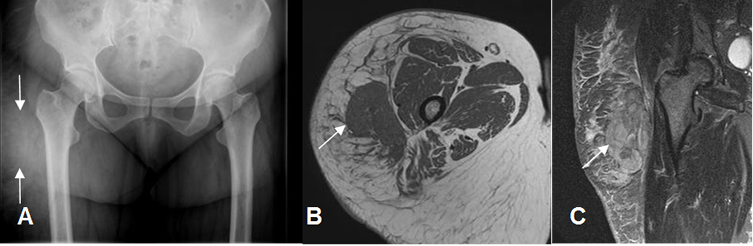

Fig 13. Hematoma muscular agudo.

A: RM coronal en T1. Colección hipointensa sobre los aductores, que corresponde a hematoma agudo.

B: RM coronal en T2 y C: RM coronal en STIR. Colección hiperintensa en ambas secuencias.

D: AngioRM coronal. Hematoma que produce efecto de masa y desplaza los vasos femorales.